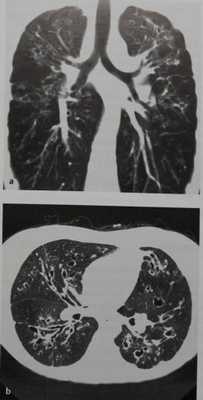

Муковисцидоз у женщины 34 лет. Помимо нерезко выраженного усиления воздушности легких на рентгенограмме грудной клетки виден тяжистый рисунок, охватывающий все легочное поле и особенно выраженный в верхнем и среднем его отделах. Корни легких укорочены и смещены кверху. Эти признаки обусловлены выраженными изменениями бронхиальной стенки и бронхоэктазами.

КТ более информативна для определения типа и объема изменений. На срезах, проходящих через легкие, видны многочисленные кистовидные и мешотчатые бронхоэктазы